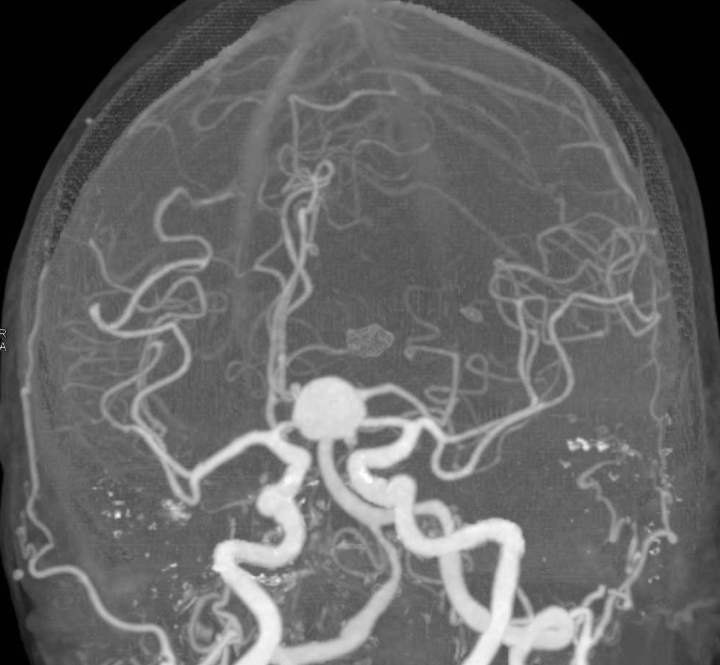

颅内动脉瘤为颅内动脉管腔局部的异常膨出部,多发生在脑底动脉环及其主要分支。直接手术仍是治疗颅内动脉瘤的主要方法,近年来开展了血管内栓塞治疗,并有发展的前景。

D,术前左VA前后位血管造影显示大量血栓形成的VA-PICA动脉瘤的灌注部分(箭头)。磁共振血...